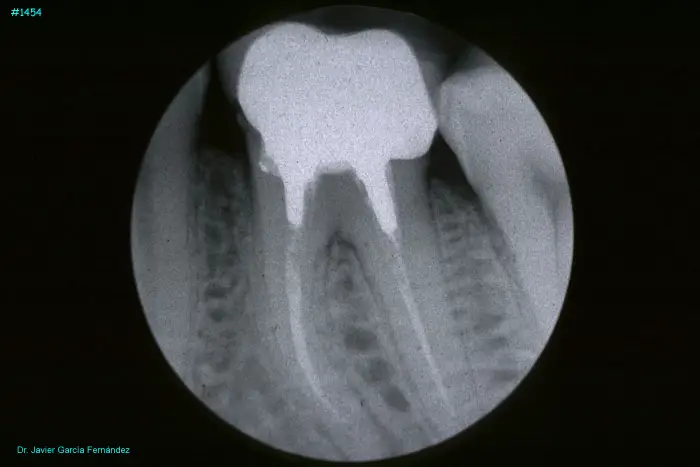

Atlas of Surgical Techniques in Periodontics. Chapter III. Atlas de Técnicas Quirúrgicas en Periodoncia